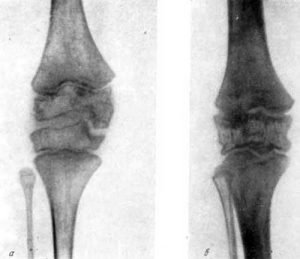

Классификация

- костный (истинный);

- фиброзный (рубцовый).

Диагноз «костный анкилоз» ставят в том случае, когда концы повреждённых костей соединяются друг с другом при помощи костной ткани на разном её протяжении. Отличие фиброзного анкилоза в том, что между концами костей есть фиброзная ткань. В ней могут быть остатки хряща или синовиальной оболочки.

Эти разновидности заболевания отличает и внешний признак: при первом типе болезни сочленения лишены подвижности, а при втором человек может слегка шевелить пальцами, рукой или ногой.

Основа распознавания анкилоза – визуализирующие методики, такие как рентгенография костей и суставов, компьютерная или магнитно-резонансная томография. С их помощью определяется сужение и прерывистость суставной щели или ее полное заращение.